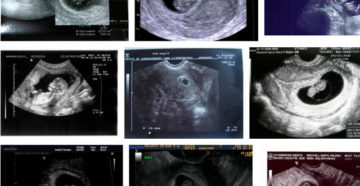

Восьмая акушерская неделя Восьмая акушерская неделя беременности, является некими переходным этапом по нескольким пунктам. Во-первых,…

8 неделя беременности – признаки, ощущения и вероятные риски Ранние сроки процесса гестации всегда сопровождаются…

Развитие плода и советы на 8 неделе беременности Этот период характеризуется увеличением гормонального фона. Женщины…